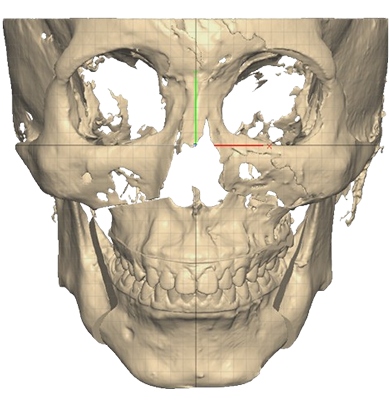

STEP 01

3D플랜에 따라 최적의 위치로 상-하악을 위치시킴

STEP 02

무턱 교정을 위해 하악을 앞으로 이동시켜 적정한 교합을 맞춤

STEP 03

플랜을 기반으로 제작된 Wafer를 장착하고 뼈를 고정

수술결과

무턱 개선 : 턱 끝 기준 14mm 전진